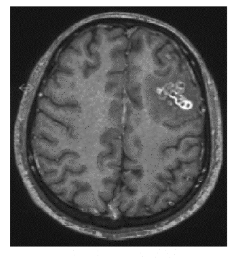

Een zestienjarige jongen kreeg tijdens zijn verblijf in Nederland regelmatig epileptische aanvallen. Uit onderzoek bleek dat deze aanvallen het gevolg waren van een varkenslintworm.

Epilepsie is een aandoening van het centrale zenuwstelsel waarbij af en toe een sterk afwijkende hersenactiviteit ontstaat: een epileptische aanval. Tijdens een epileptische aanval kunnen ongecontroleerde spiersamentrekkingen optreden, en kan de patiënt het bewustzijn verliezen.Op de MRI-scan van het hoofd van de jongen (afbeelding 1) zijn holtes (cysten) te zien. Eromheen is oedeem te zien (afbeelding 2). |